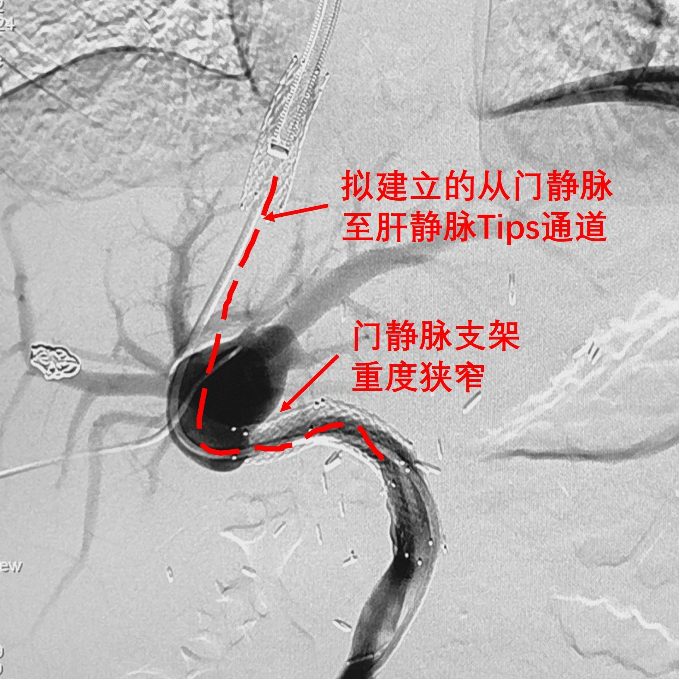

图4.经肝静脉支架穿刺门静脉成功

图5门静脉重度狭窄。拟建立的从门脉支架至肝静脉支架的Tips分流道